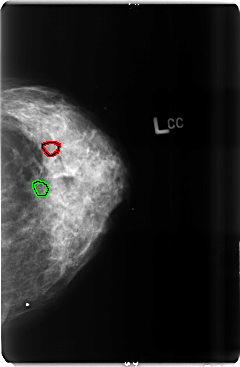

B_3509_1.LEFT_CC

LEFT_CC LINES 4768 PIXELS_PER_LINE 3112 BITS_PER_PIXEL 12 RESOLUTION 50 OVERLAY

FILE: B_3509_1.LEFT_CC.OVERLAY

TOTAL_ABNORMALITIES 2

ABNORMALITY 1

LESION_TYPE CALCIFICATION TYPE PLEOMORPHIC-FINE_LINEAR_BRANCHING DISTRIBUTION CLUSTERED

ASSESSMENT 4

SUBTLETY 3

PATHOLOGY MALIGNANT

TOTAL_OUTLINES 1

BOUNDARY

ABNORMALITY 2